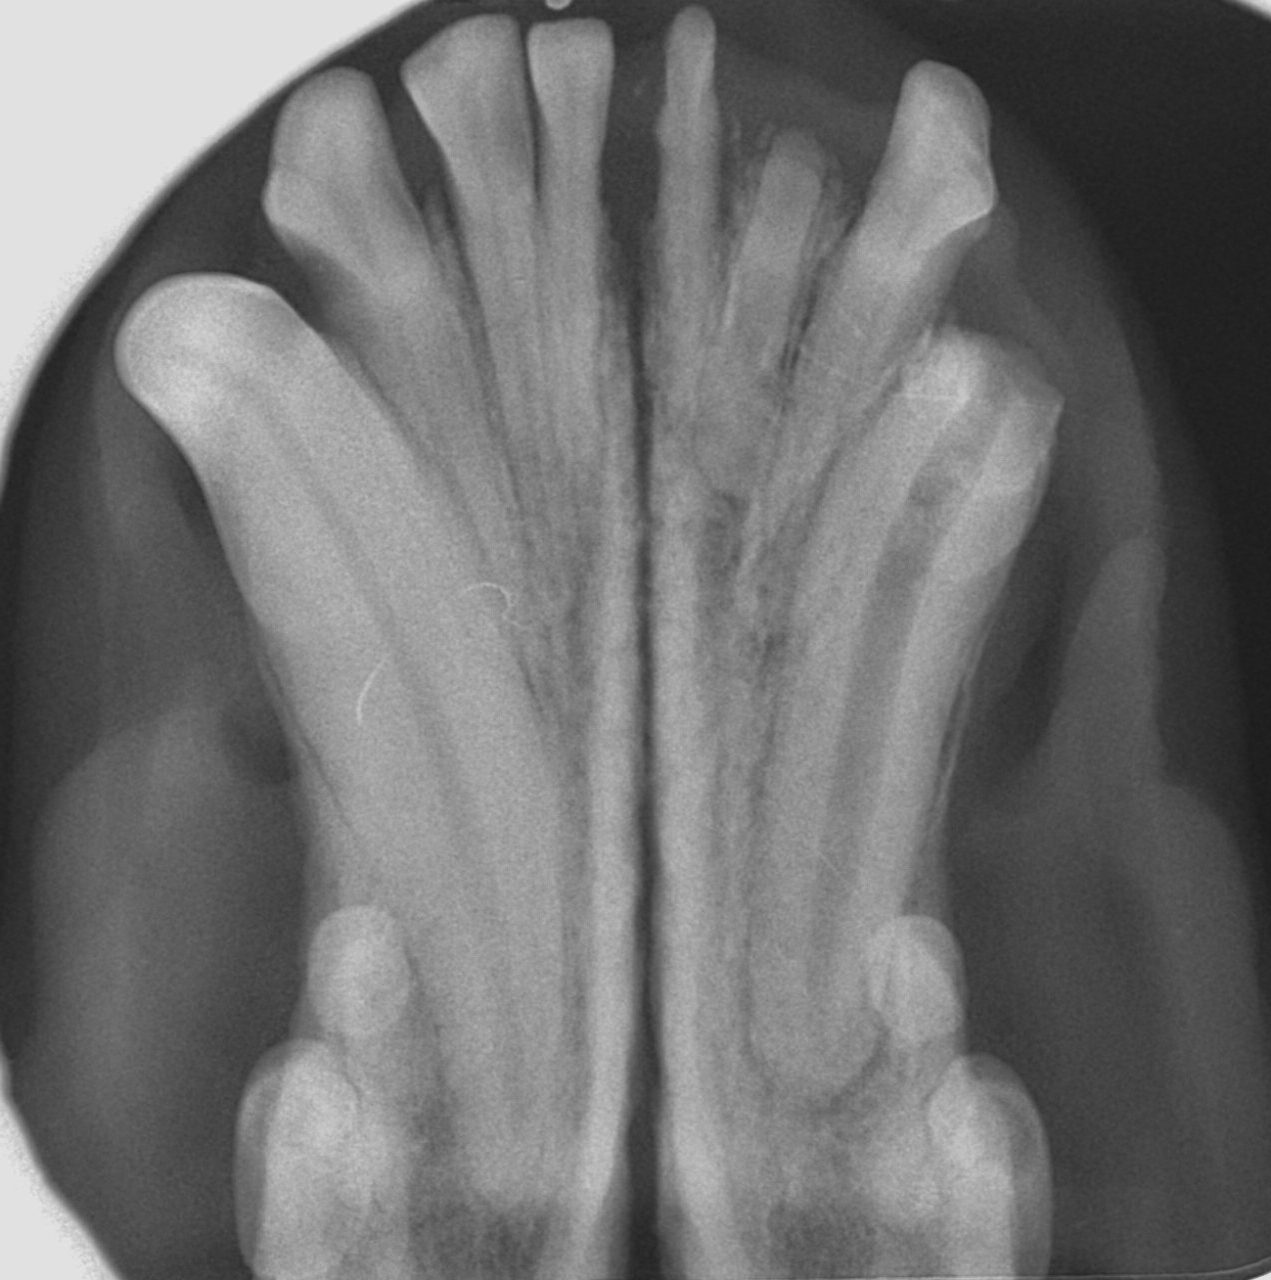

Alteración en el número y posición de los dientes

Ausencia dental

Cuando en una exploración visual de la boca observamos una ausencia dental debemos hacer una radiografía que nos indique la causa, que puede ser de origen genético o deberse a alteraciones sufridas durante las primeras etapas del desarrollo dental o a lo largo de la vida del animal.

A nivel radiológico nos podemos encontrar con varias situaciones:

- Ausencia del diente porque no se ha formado (agenesia).

- El diente no ha erupcionado por estar ectópico (fuera de su área anatómica).

- El diente está incluido o impactado (cuando no logra erupcionar o lo hace parcialmente por diferentes causas).

También puede ser debida a la pérdida dental (por EP, por ejemplo) o a fracturas de corona en las que quedan restos de estructuras dentales bajo la encía. Por tanto, dependiendo de ello, decidiremos el enfoque terapéutico que tomaremos en cada paciente con ausencia dental. (imágenes 14-17).